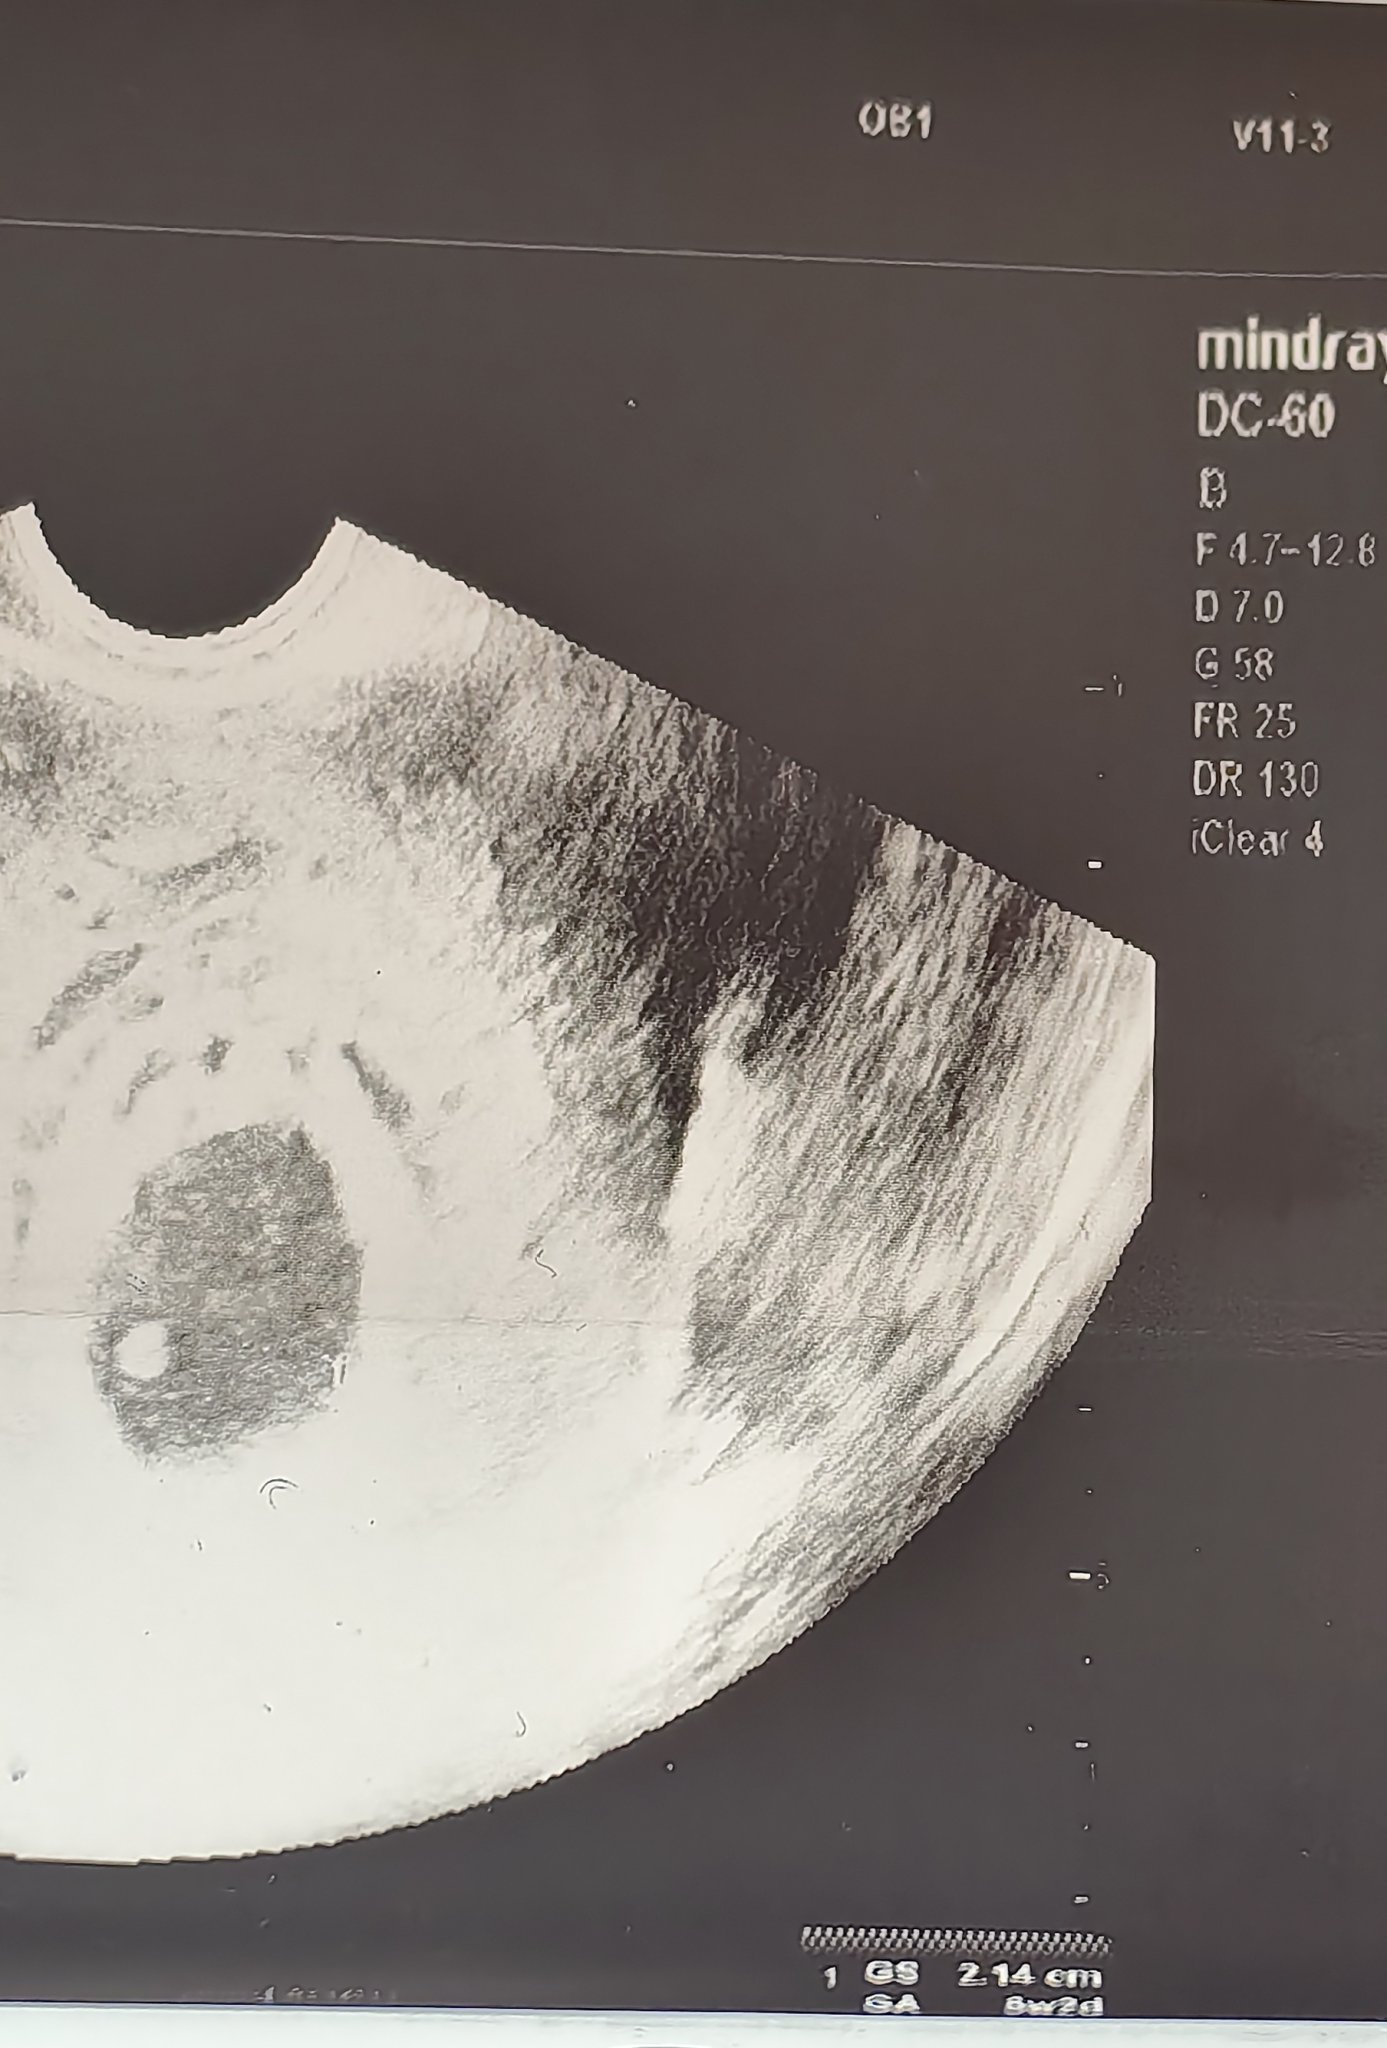

Какво представлява изображението от ехографията на 5-седмична и 2-дневна бременност?